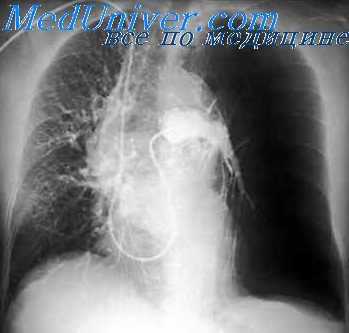

Присоединение атомов йода к молекулам органических веществ позволило создать новые, менее токсичные рентгеноконтрастные вещества. В 1925 – 1929 гг. компанией Эрнеста Шеринга велась активная разработка органических йодсодержащих КВ; уже в 1929 году Swick впервые выполнил в/в урографию с помощью йодсодержащего препарата уроселектан (Schering AG). В 1950-х годах в клиническую практику были внедрены йодсодержащие КВ из группы диатризоатов (урографин, ренографин, гипак), которые были менее токсичны, чем прежние препараты. Следующей значимой вехой в интервенционной кардиологии стало выполнение первой селективной коронарографии F. Sones в 1958 году (с помощью гипака).

В 1964 году шведский радиолог Torsten Аlmen разработал новую концепцию строения КВ, и в 1969 году по его заказу было синтезировано первое неионное контрастное вещество Амипак. Необходимо отметить, что после внедрения неионных КВ частота осложнений после выполнения ангиографии значительно уменьшилась. Как известно, первую баллонную ангиопластику коронарных артерий у человека выполнил в 1977 году А. Gruentzig, а первое стентирование коронарных артерий – в 1986 году U. Sigwart (Швейцария) и J. Puel (Франция), в разных клиниках, независимо друг от друга. Пионеры интервенционной кардиологии выполняли свои первые вмешательства уже с помощью более безопасных неионных КВ.